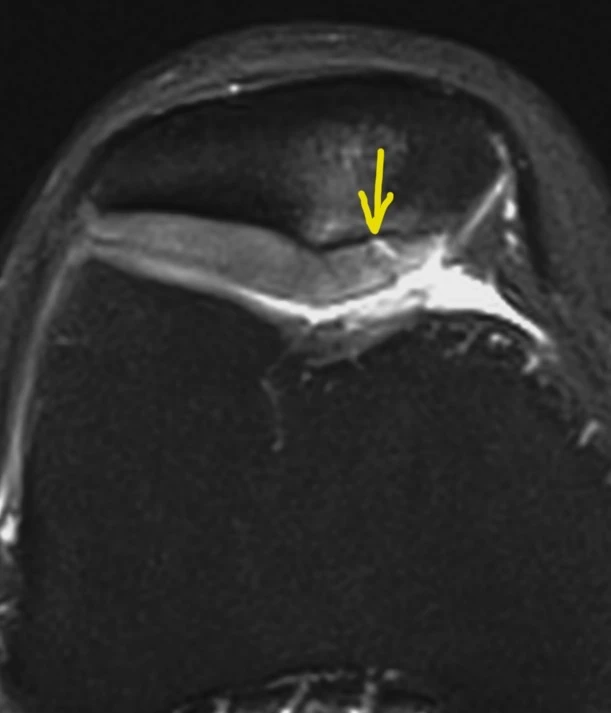

А вот вдогонку ещё костное повреждение Банкарта, парень 20 лет. Последствия переднего вывиха плеча.

Из-за отрыва сухожилия подлопаточной мышцы вывихнулось медиально сухожилие длинной головки бицепса. Сухожилие подлопаточной мышцы является одновременно удерживателем длинной головки бицепса в межбугорковой борозде, вплетаясь в малый бугорок плеча и как бы продолжаясь в поперечную связку (связку Броди), которую некоторые считают не истинной связкой, а частью сухожилия надостной мышцы.